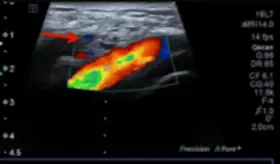

Las imágenes mostraron una aorta abdominal significativamente dilatada, con un diámetro transversal de 4.4 centímetros, muy por encima del límite normal de 3 centímetros.